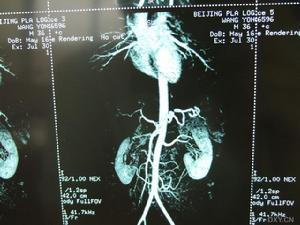

《布-加綜合徵的診斷與治療》2.ct、mra具有較高的診斷價值。